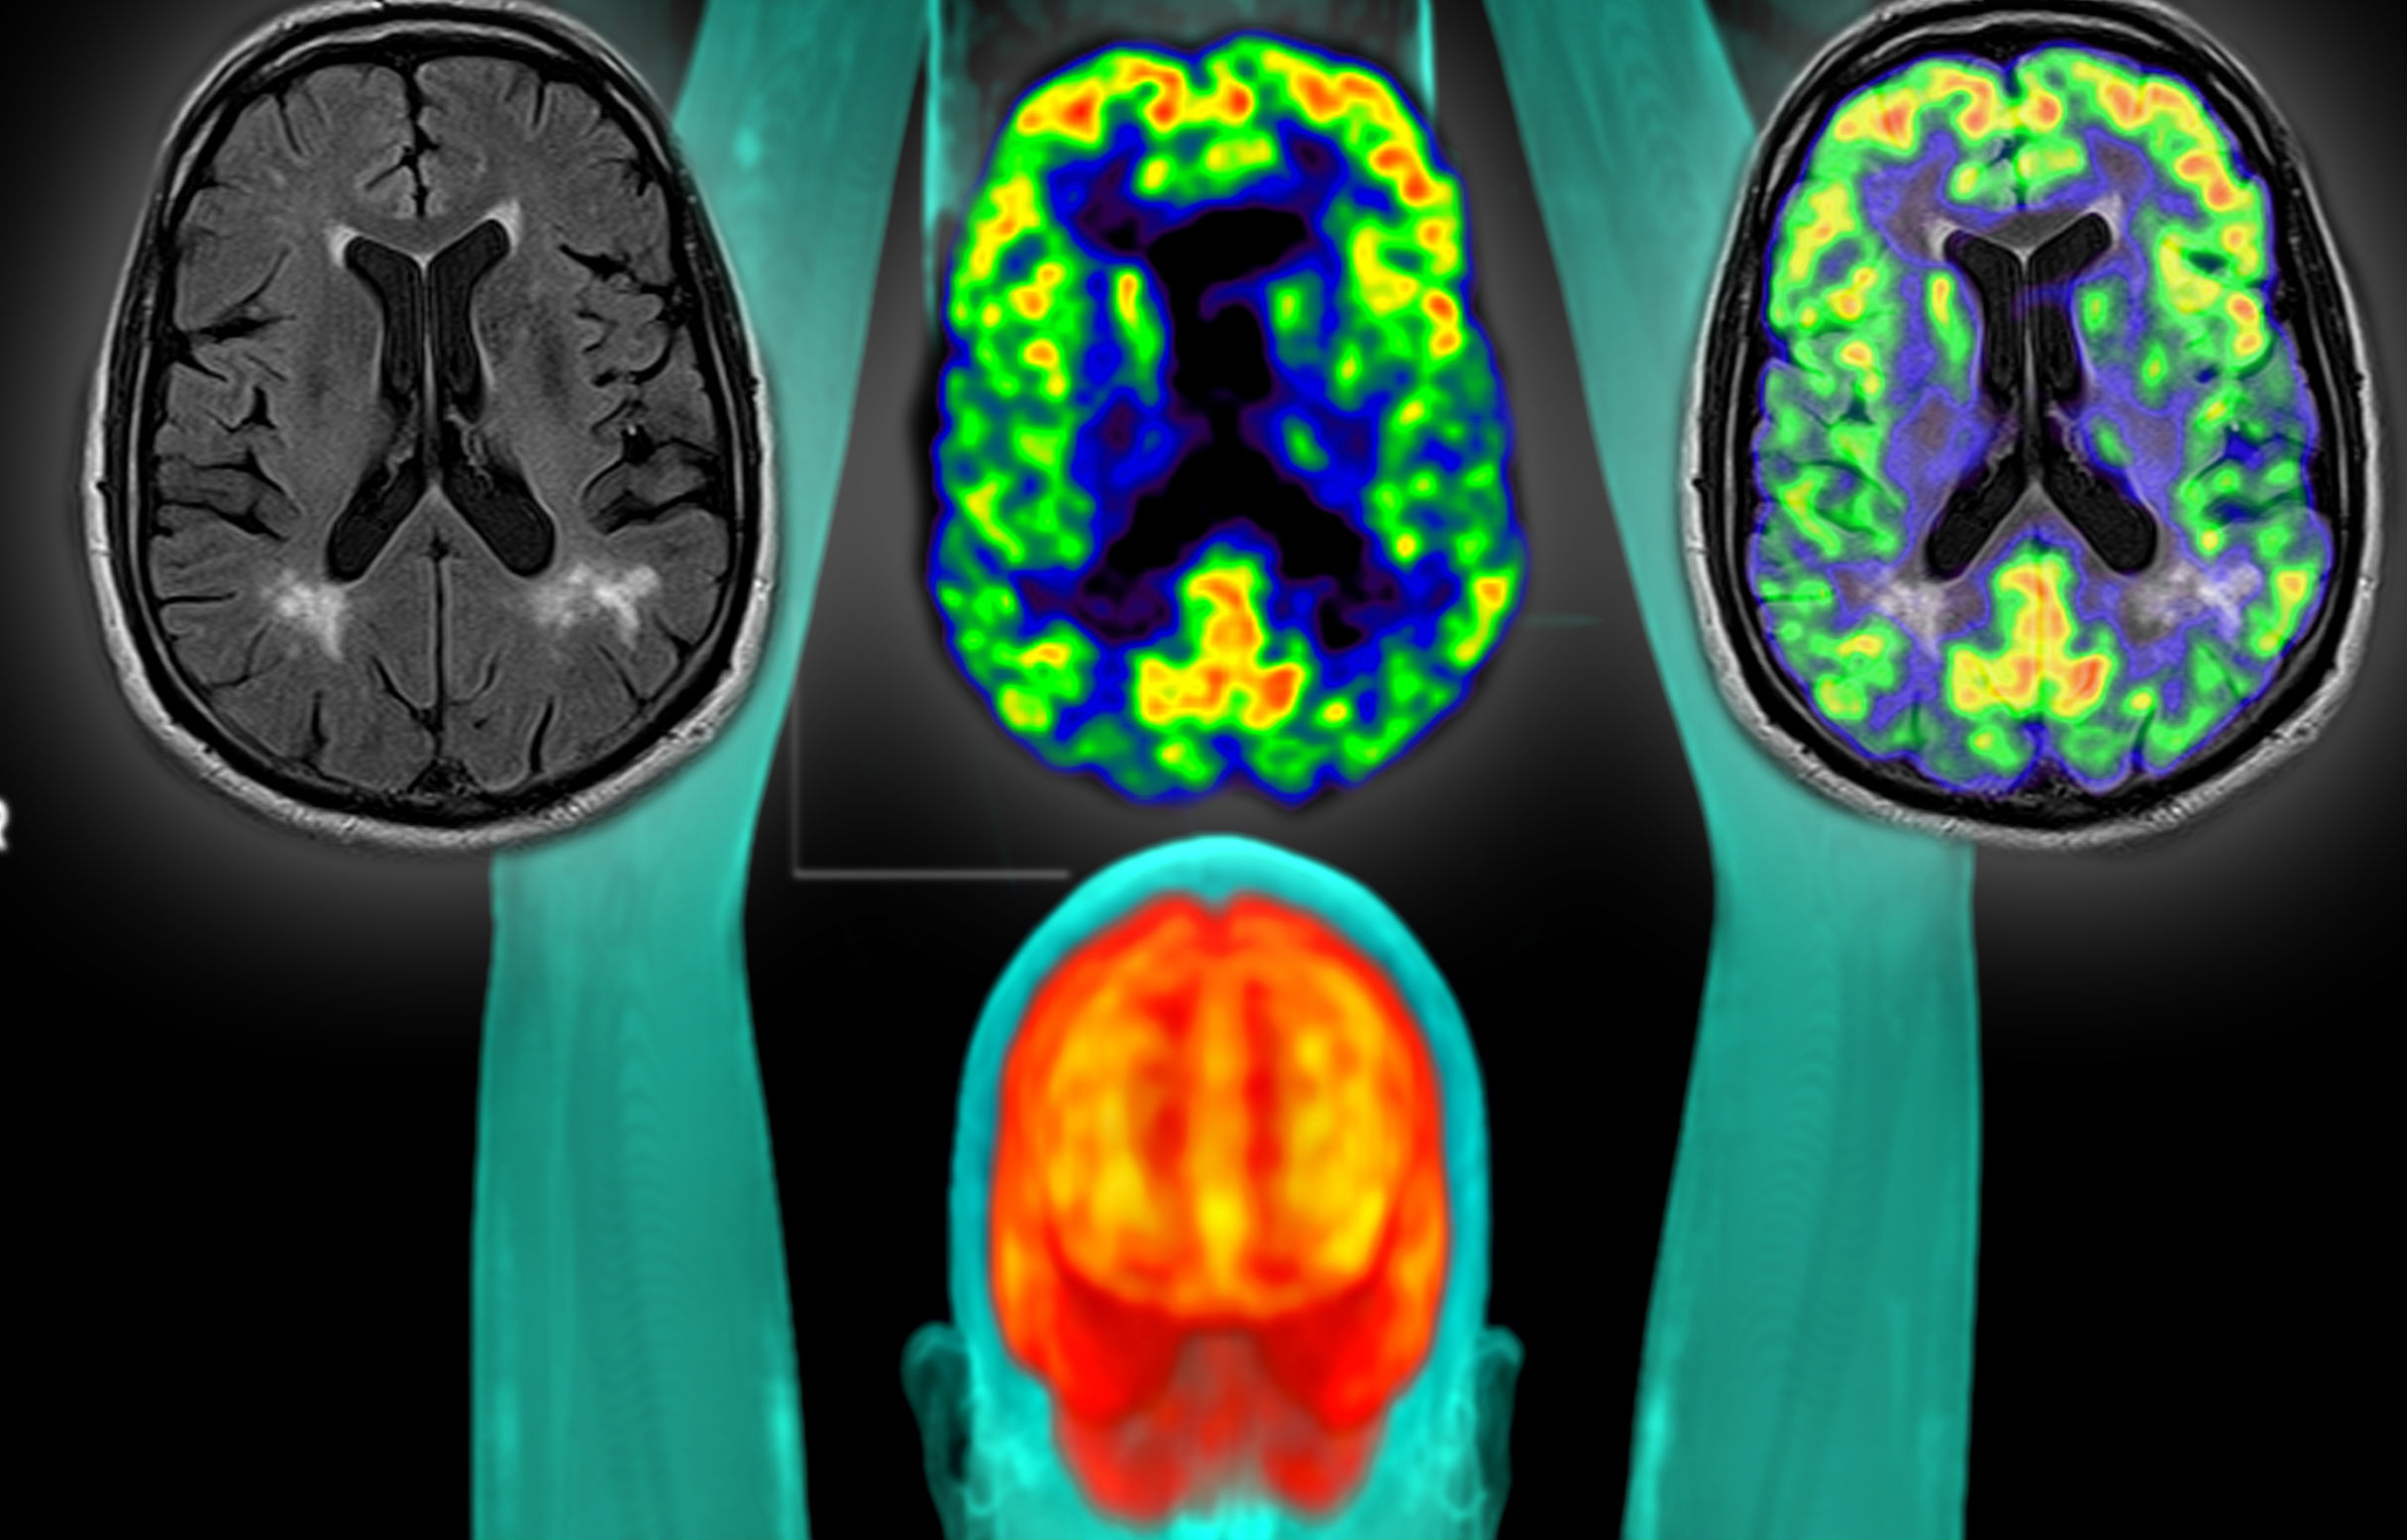

Zależy nam, by była to ocena jak najbardziej wszechstronna. Będzie na pewno kilkadziesiąt różnych pomiarów i badań. Chcemy dokonać analizy pacjenta pod różnymi aspektami, nie tylko stricte medycznymi. Poczynając od aspektu społecznego czy socjalnego, psychologicznego, przez ocenę obwodów ciała, przez badania krwi, badania usg, czy na badaniach rezonansu magnetycznego całego ciała kończąc. Ostatecznie, jakie badania będą realizowane, to jest jeszcze ustalane.